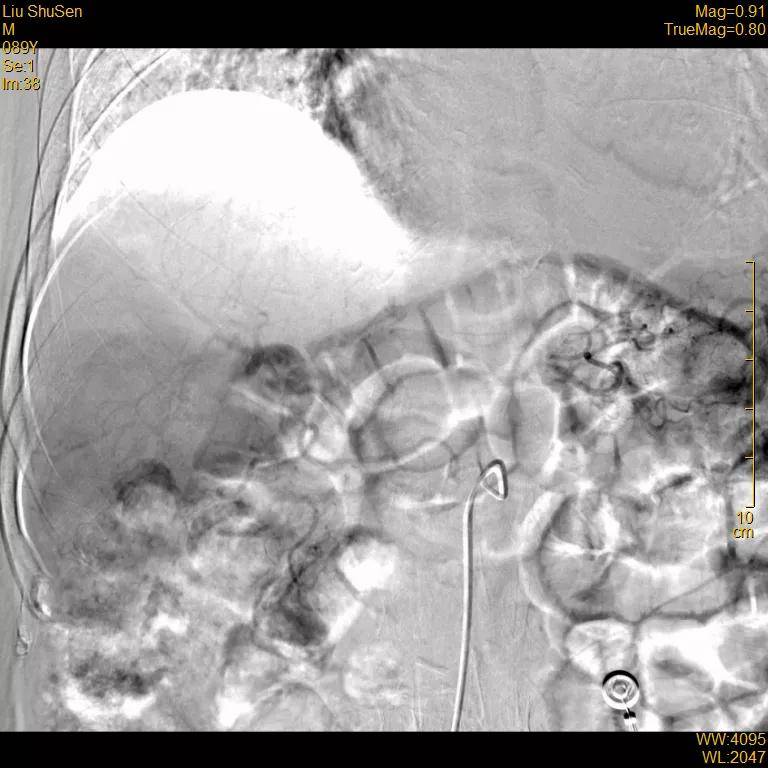

超选至肝右动脉分支2造影+栓塞

栓塞材料:表柔比星60mg+载药

微球、碘油;明胶海绵

文章图片

复查造影:原肿瘤染色不复显影